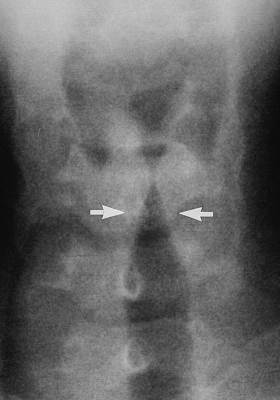

Диагностические меры

Если у человека возник стеноз горла, то обязательно нужно, чтобы приехала неотложная помощь. Ведь с каждой минутой отек усугубляется, и это может привести к летальному исходу.

Врач сделает общий осмотр пациента, аускультацию (послушает легкие), измерит артериальное давление, пульс, частоту дыхания и сердечных сокращений, осмотрит горло.

При подобном состоянии, врач может заподозрить рубцовую форму вследствие химического и термического поражения, травматический стеноз, острый эпиглотит, другие состояния обструктивно-констриктиного типа острой дыхательной недостаточности.

В дифференциальной диагностике помогут причины и анамнез заболевания.

В стационаре, пациенту можно сделать ларингоскопию (прямую и непрямую), бронхоскопию.

Другие эндоскопические методы, с помощью которых можно определить степень поражения, причину патологического состояния, ширину голосовой щели.